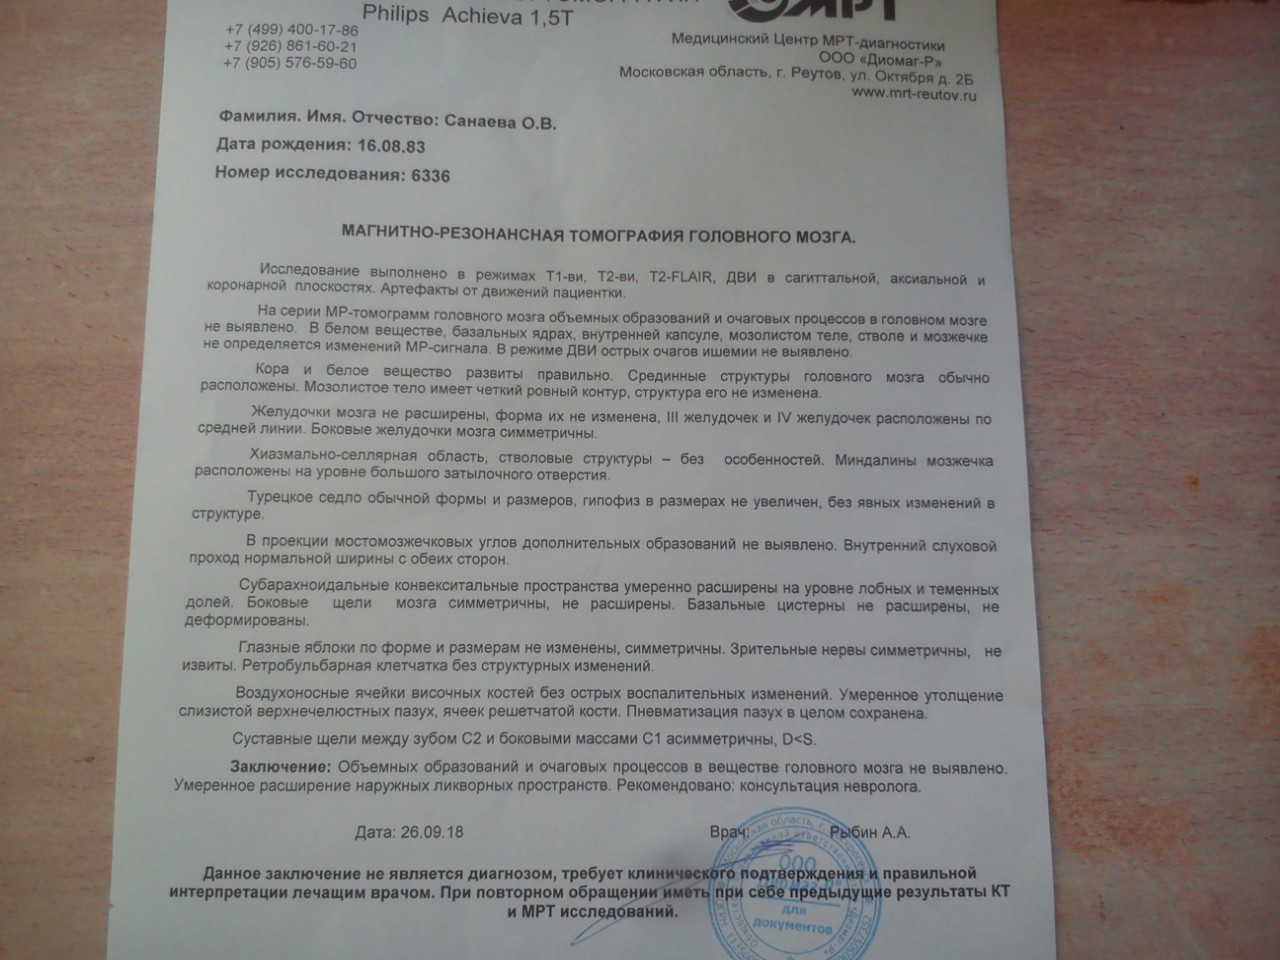

МРТ головного мозга: Расшифровка снимков и Интерпретация

Раздел: Визуальные уроки